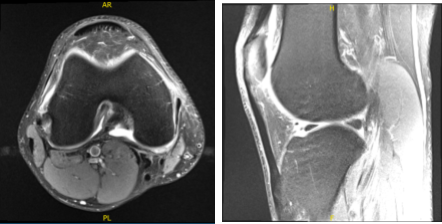

MRIs were reviewed and discussed during the visit. The results have shown complex medial meniscus tear and reactive medial collateral ligament sprain. Very small joint effusion.

MRI-3T Right Knee non-contrast